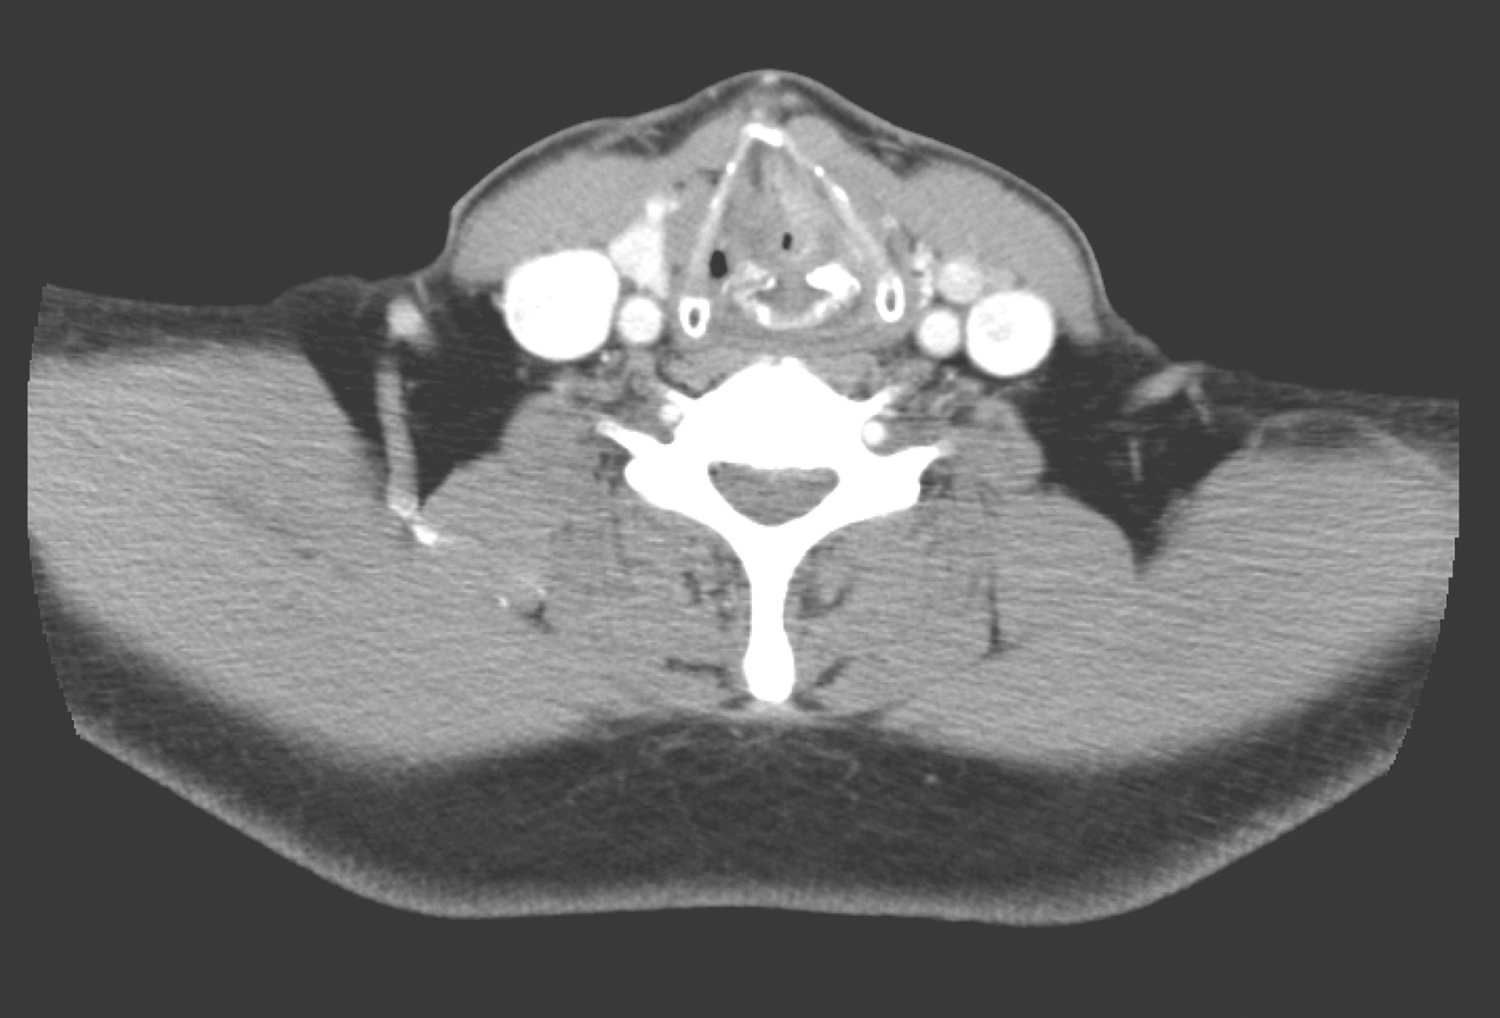

3.2017年2月14日颈胸部CT

左侧声带、室带局部软组织增厚,约1.4cm×0.5cm,形态不规则,可见强化(图2),会厌软组织略厚。气管右旁小淋巴结,约0.6cm×0.4cm,余颈部、纵隔、双肺门未见肿大淋巴结。双肺未见明确结节及实变。双侧胸腔、心包未见积液。

检查所见:

(1)左侧声带、室带所见,结合镜检可符合喉癌。

(2)右上纵隔、气管右旁小淋巴结,建议随诊。

图2 颈部增强CT示左侧声带、室带局部软组织增厚伴强化